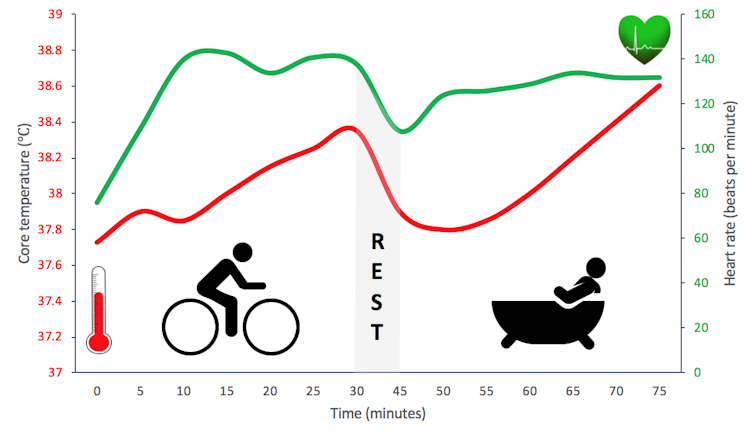

Membre d’un groupe recherche à l’Université de Coventry, j’ai comparé les similitudes et les différences entre les réactions physiologiques résultant de la pratique de l’exercice physique ou d’une augmentation de température. Pour ce faire, j’ai demandé à des volontaires de prendre un bain chaud pendant un temps donné, ou faire du vélo (avec une intensité modérée) sur une durée équivalente. Si l’exercice s’est avéré plus apte à augmenter la dépense énergétique des participants, nous avons néanmoins constaté dans les deux situations des élévations comparables de leur température corporelle et de leur fréquence cardiaque.

J’étudie actuellement la possibilité de prolonger et d’intensifier les bienfaits de l’exercice physique en prenant un bain chaud après l’effort. Les données préliminaires que j’ai recueillies semblent prometteuses. Reste désormais à effectuer des mesures plus invasives, comme des analyses sanguines, afin de déterminer si l’application de chaleur après l’exercice peut augmenter le nombre de molécules circulantes impliquées dans l’amélioration de l’état des vaisseaux sanguins. Bien que ces travaux n’en soient qu’à leurs débuts, nous pensons qu’essayer de maintenir l’augmentation de la température corporelle après un exercice physique permettrait probablement d’optimiser les bénéfices dudit exercice pour la santé.